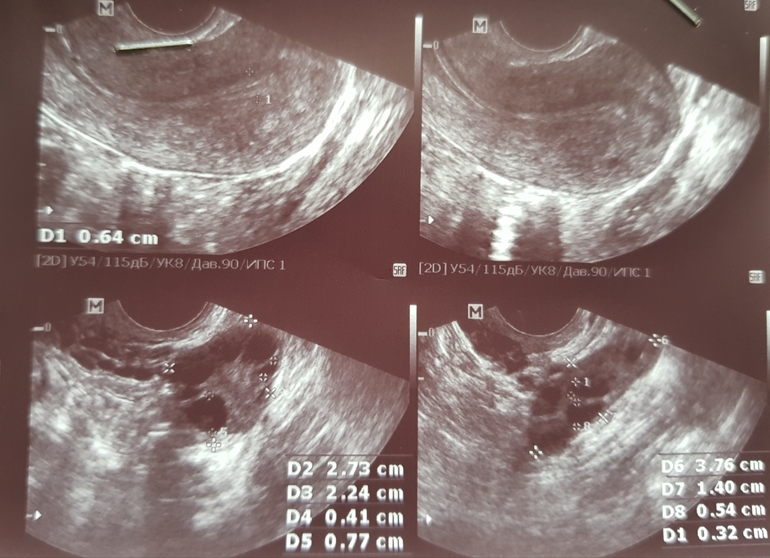

В этом цикле что то странно, прыщи на лице, грудь немного чувствительна прям сразу еще до о. Сегодня 10дц, пошла я на узи посмотреть что там. В яичниках по 7-8 фоликов, в одном 3-5мм и в другом 7-8мм. Доминантного я так поняла еще нет. Эндометрий узистка сказала маленький 6мм и не соответствует 1й фазу цикла, имеет какие то включения. Намекнула что в этом цикле не получится.

В прошлый раз на 9й дц дф был уже 13мм и эндометрий 7,7.